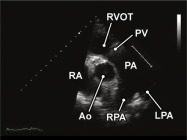

| 2.7. Mặt cắt trục ngắn cạnh ức (ngang mức các đại động mạch) khu trú vào van động mạch phổi

|

||||||||

|

|

Cửa sổ siêu âm cạnh ức Mặt cắt trục ngắn cạnh ức Xoay đầu dò 90O từ mặt cắt trục dài cạnh ức và ngửa đầu dò lên trên. |

Động mạch chủ (Ao)

Nhĩ phải (RA) Đường ra thất phải (RVOT) Van động mạch phổi (PV) Động mạch phổi (PA) Các nhánh phải (RPA) và trái (LPA) của động mạch phổi |

|||||